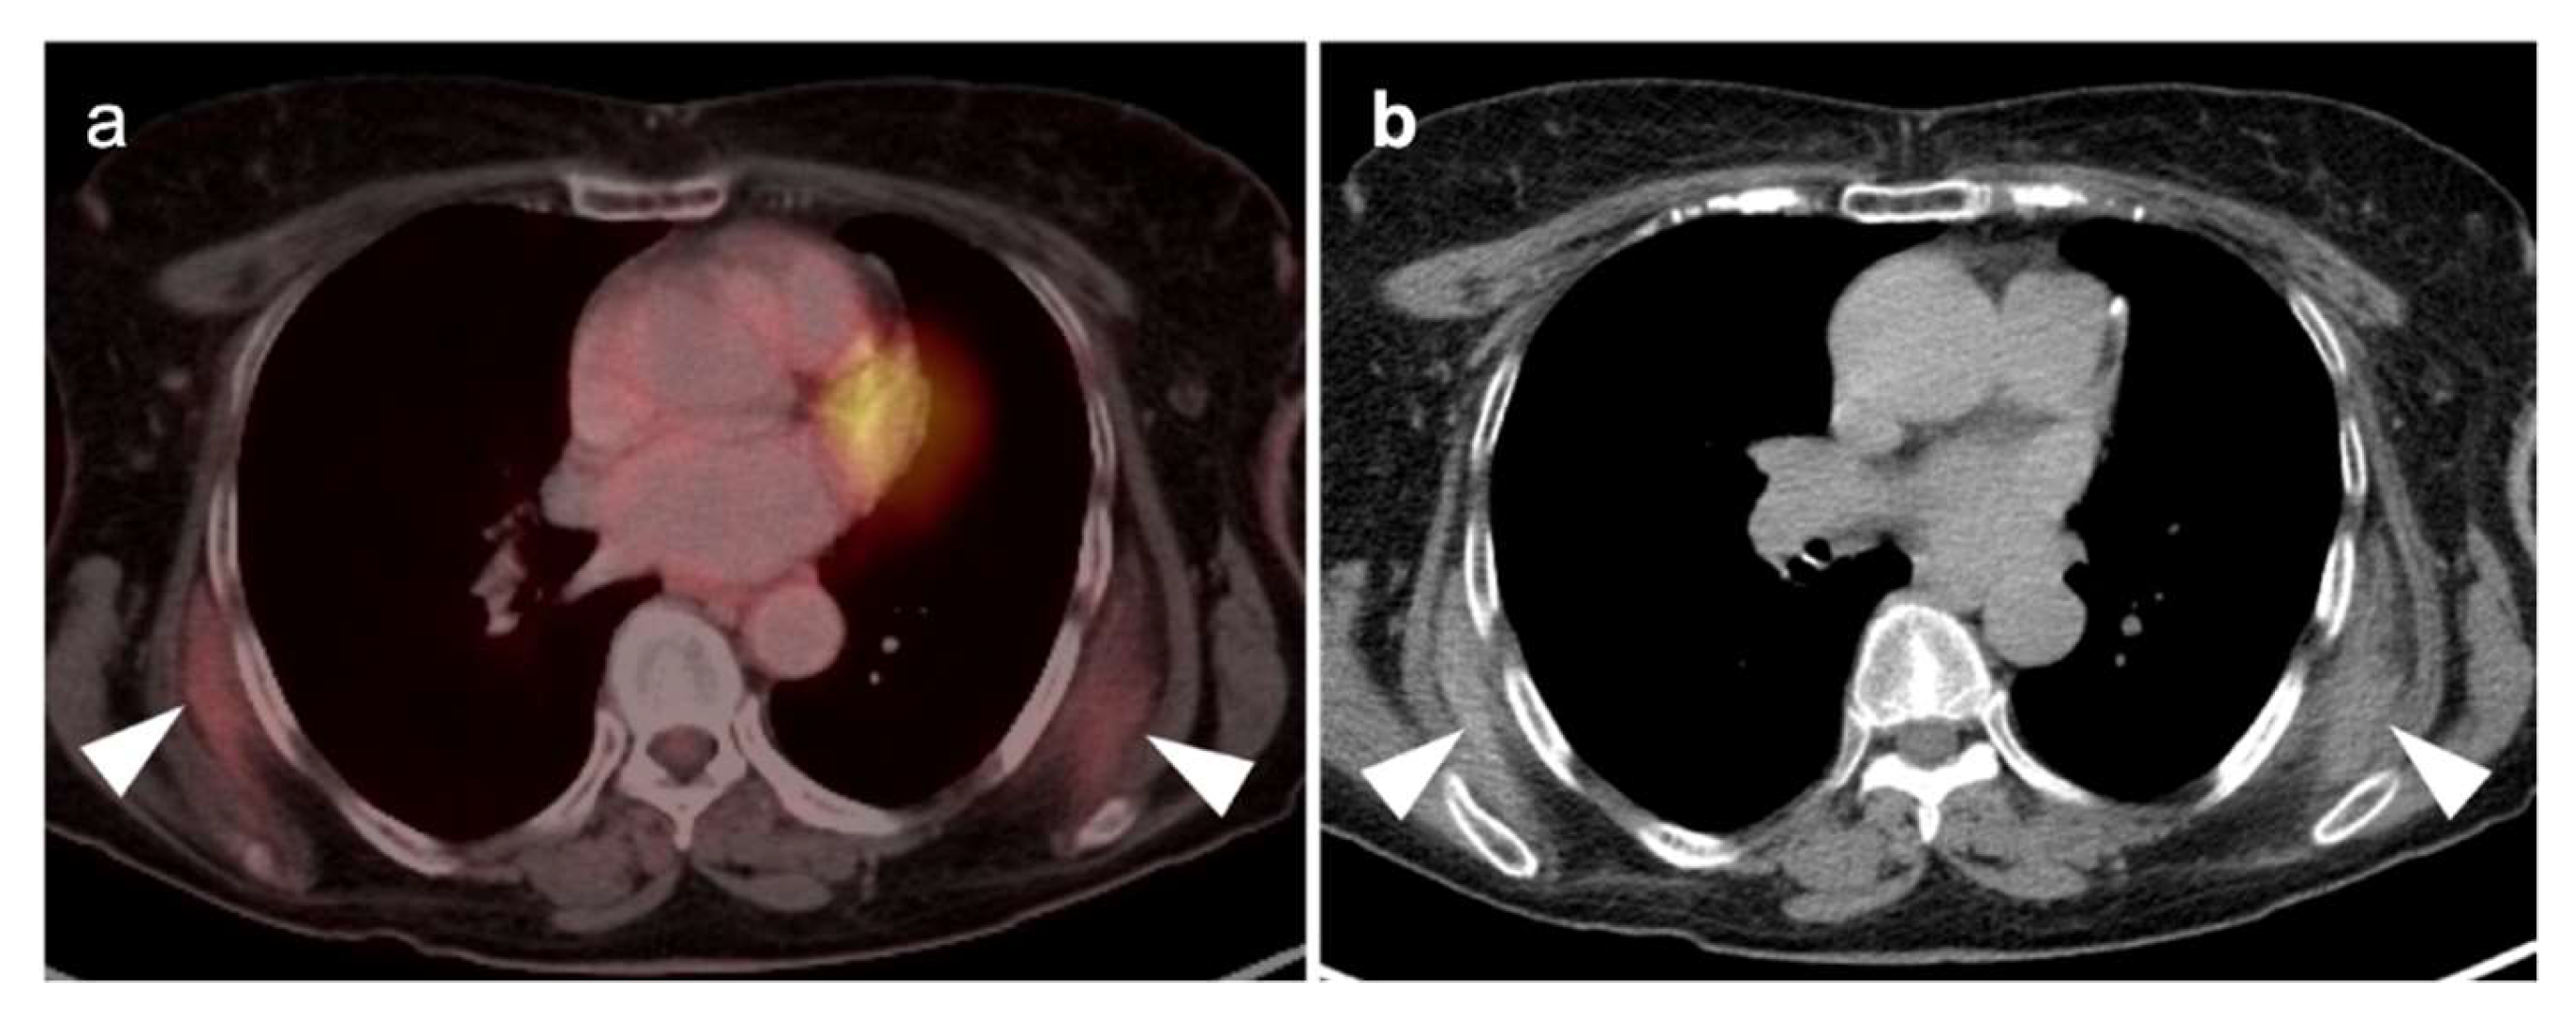

In diagnostic imaging of MPM, FDG PET-CT, whole-body MRI and PET-MRI show superiority over conventional CT [51]. MPM is typically intensely hypermetabolic on FDG PET-CT, making it highly amendable to staging by this method (Figure 13 and Figure 14). Hypermetabolic pleural thickening is typically associated with calcified pleural plaques but can be mimicked by hypermetabolic host inflammatory reaction to talc pleurodesis, empyema, and other pleural inflammatory disease, or by other subpleural malignant processes (Figure 15) [52]. NCCN endorses the use of FDG PET-CT to stage patients only if they are being considered for surgery [53]. However, FDG PET-CT may under-stage mediastinal or nodal disease in MPM and is typically best used for assessment of distant metastases [54]. PET-CT should be done prior to contemplated talc pleurodesis. NCCN also supports the use of FDG PET-CT for mediastinal assessment based on possible evidence of disease progression following induction chemotherapy.

In summary, MPM is typically intensely hypermetabolic on FDG PET-CT, but can be mimicked by hypermetabolic host inflammatory reaction to talc pleurodesis, or other inflammatory or malignant pleural processes. The best use of FDG PET-CT for staging should be reserved for patients considered for surgery or for assessment of suspected disease progression despite induction chemotherapy, with the realization that FDG PET-CT may under-stage mediastinal or nodal disease.